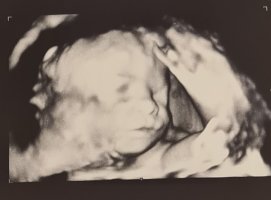

12+0 i dag!